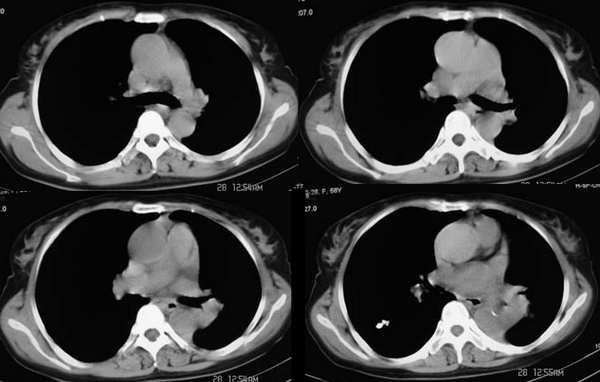

左侧胸廓容积缩小,纵隔左移,左下肺支气管闭塞.考虑中心型肺癌并左肺下叶不张,建议纤支镜.

属典型的左下肺中央型肺癌——左下分叶状肺肿块、支气管阻断、左下肺不张,纵隔淋巴结肿大。

左侧肺部体积缩小,纵隔向患侧偏移,左下肺支气管阻塞,中央型肺癌合并肺不张可能性大。

左下肺团块状软组织密度影,呈分叶状,边界清,未见小毛刺,左下肺支气管阻塞,纵隔见肿大淋巴结,考虑左下肺中央型肺癌伴纵隔淋巴结肿大,建议支纤镜检查。

左侧胸廓容积缩小,纵隔左移,左下肺支气管闭塞.考虑中心型肺癌并左肺下叶不张,建议纤支镜.右肺及肺门区钙化灶,有下肺紧贴胸膜的小结节影